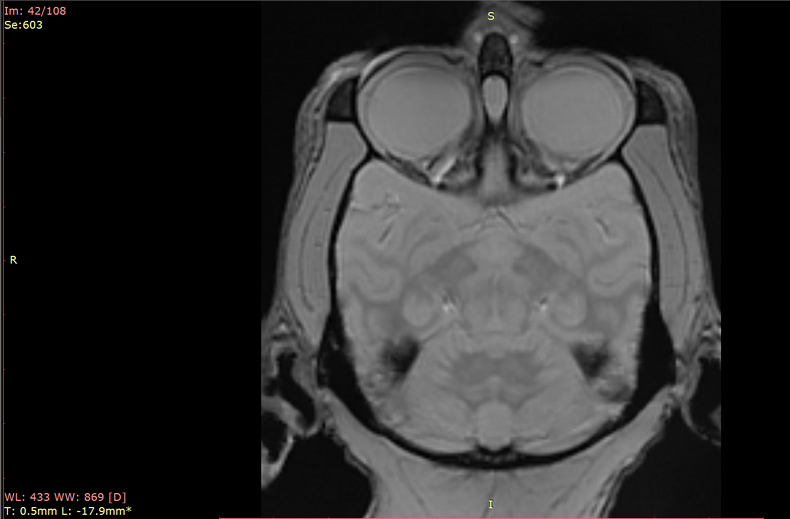

预定本数据集为收集到的2023年中国科学院昆明动物研究所实验动物中心7只北平顶猴(青年,雌性4只6-8岁,雄性3只7-9岁)的脑部核磁共振扫描数据,主要扫描序列包括T1w、T2w、DTI、EPI、GRE、MTP等。通过该数据可进一步了解到健康青年北平顶猴脑部影像学特征,并为未来的研究提供重要的依据。

a.物种:北平顶猴

b.实验动物信息

样本数量:7只

年龄分布:6-9岁

重量分布:6-11kg

性别分布:雌性4只,雄性3只

c.扫描仪规格

扫描仪类型:联影uMRNX 3.0T磁共振扫描仪器

线圈:12通道专用头线圈

d.扫描程序

动物福利伦理:由中国科学院昆明动物研究所实验动物福利伦理委员会批准

动物护理和饲养:中国科学院昆明动物研究所实验动物中心

麻醉程序:丙泊酚维持麻醉

扫描体位:俯卧头先进